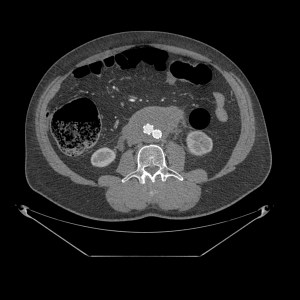

SIGNO DE LA AORTA FLOTANTE (Floating aorta sign):

Representa el crecimiento y coalescencia de conglomerados adenopáticos que desplazan la aorta lumbar hacia adelante, despegándola de la columna. Este signo lo producen algunos tumores, en especial el Linfoma. Así, da la impresión de que la aorta está «flotando» inmersa en una masa de partes blandas retroperitoneal que se ha formado por el crecimiento de las adenopatías de las cadenas periaórticas, pericavas e interaortocavas, las cuales finalmente se han unido. Otro signo muy útil es el signo del Sandwich, donde se observa, en un TC con contraste, como la masa envuelve los vasos y la grasa del mesenterio.

Aparte del linfoma, en las otras etiologías, puede no existir el desplazamiento de la aorta lumbar (algunas metástasis, fibrosis), puede haber menos coalescencia de los conglomerados adenopáticos (TBC, micobacaterias atípicas), puede observarse áreas hipoatenuadas en su interior de necrosis (leiomiosarcoma) o con densidad grasa (liposarcoma) o las adenopatías pueden tener un realce ávido de contraste (E. de Castleman). En la fibrosis retroperitoneal la atenuación con contraste es más uniforme, la localización suele ser infrarrenal, sin desplazamiento anterior de aorta y con afectación de uréteres. Las posibilidades son numerosas y cada una tiene sus características.